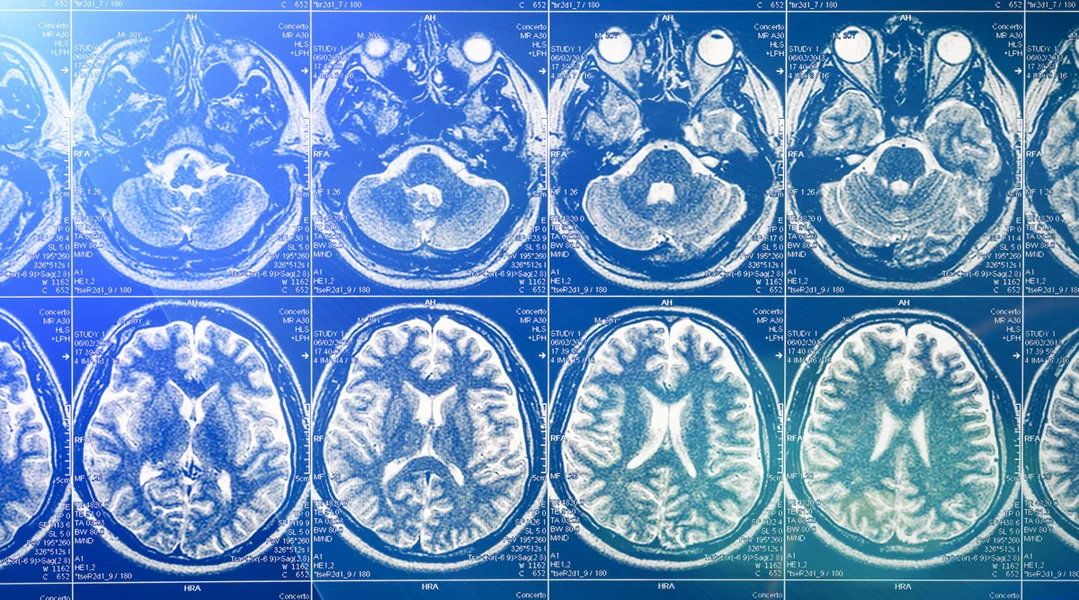

D'Gehir verännert sech, wann ee léiert, seet de Steve Masson. Dat géife Studie vun de 90er Joren u beleeën. Fir d'Etüden hunn d'Fuerscher op den IRM zréckgegraff - e medezinescht Instrument, dat duerch magnéitesch Vibratioune prezis Biller vum Kierper realiséiert. Den IRM géif et erméiglechen, d'Aktivitéite vum Gehir opzezeechnen.